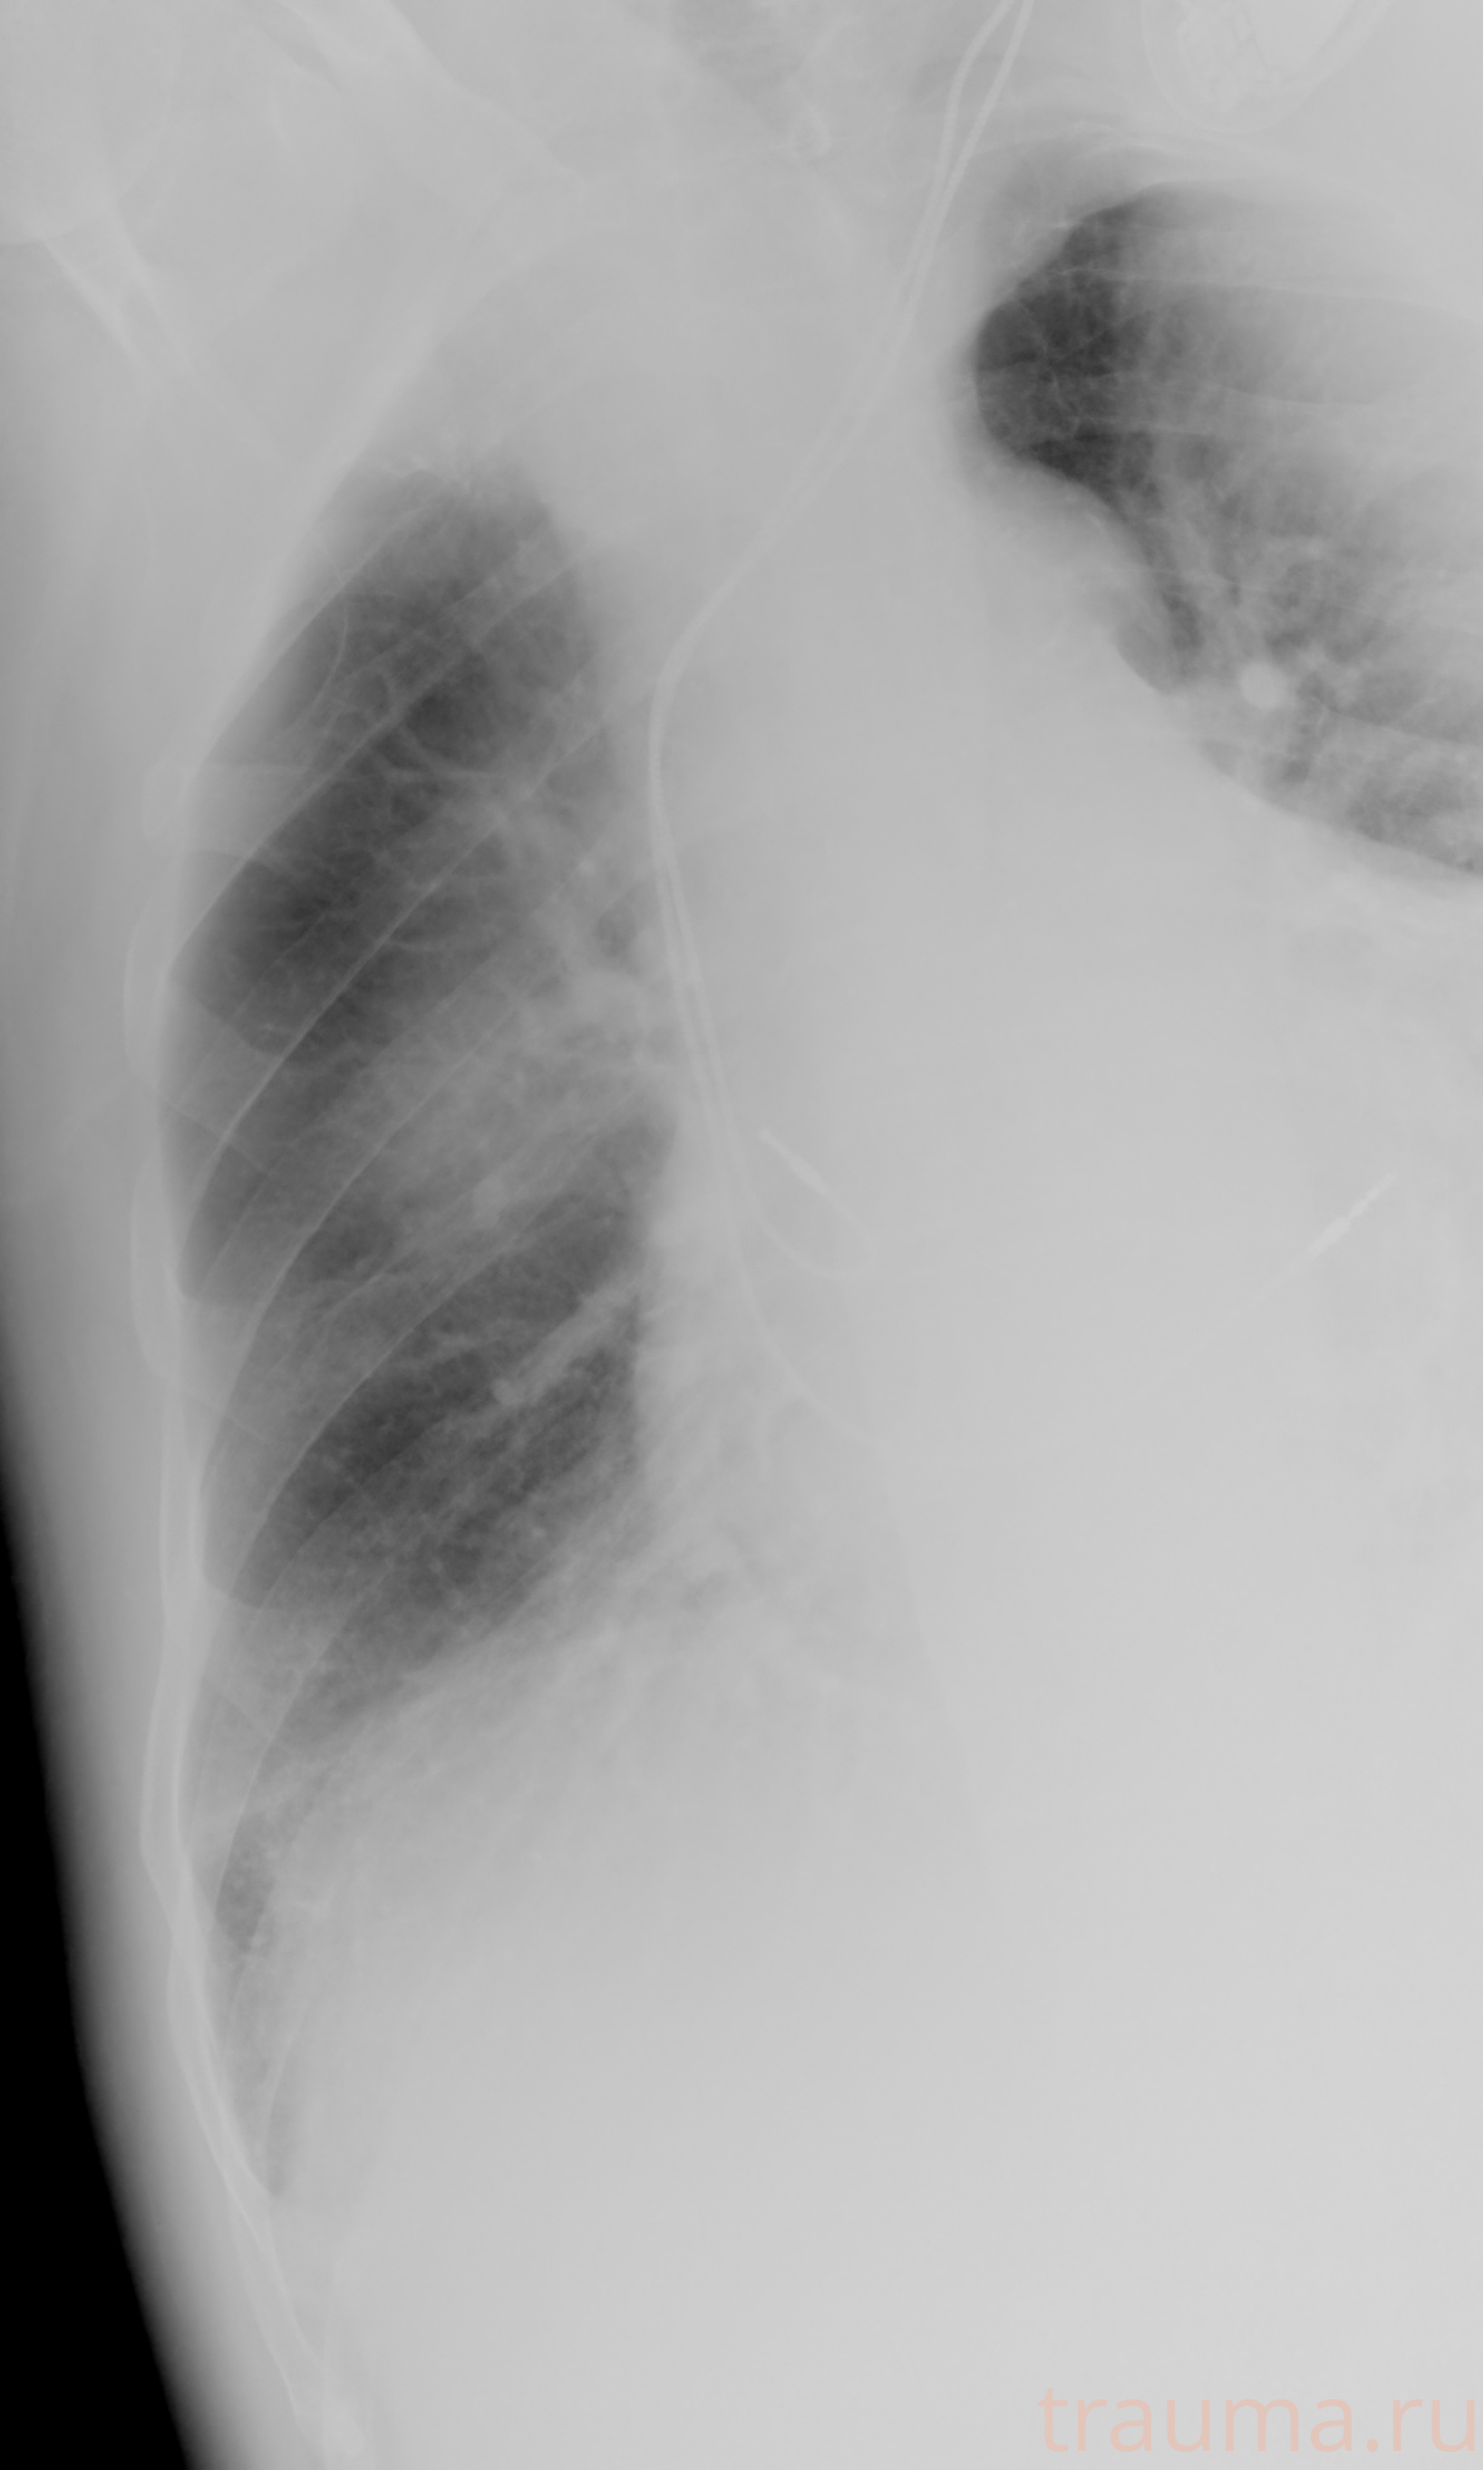

Рентген на дому: по вашему адресу приезжает врач-рентгенолог, травматолог-ортопед с мобильным рентгеновским аппаратом, проводит диагностику травмы или заболевания, делает необходимые рентгенограммы, дает рекомендации по дальнейшему лечению. Получить качественные снимки в домашних условиях возможно благодаря уникальной методике, разработанной МосРентген Центром для института  Склифосовского